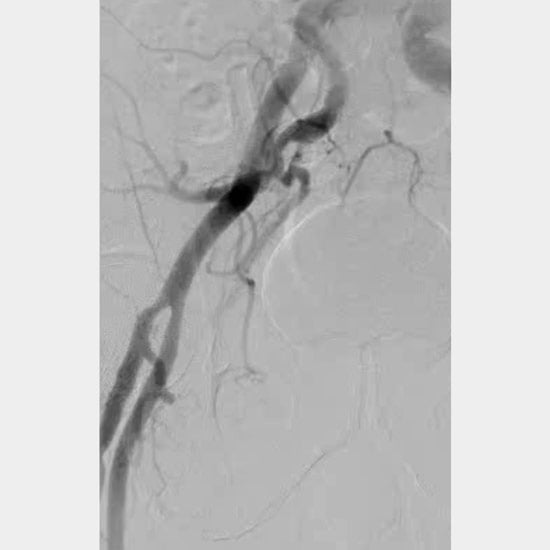

Figure 1H: Femoral angiogram demonstrated successful percutaneous closure.